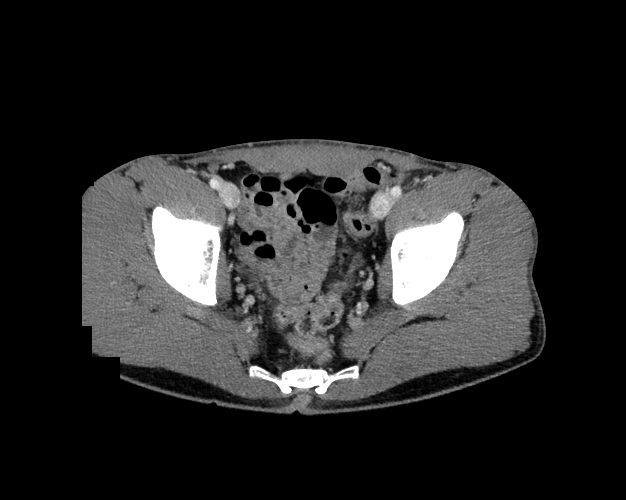

Pelvis

Covers pelvic MRI anatomy.